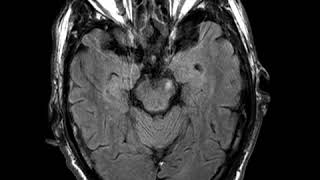

Primary Cns Lymphoma

Cns C9 Primary Cns Lymphoma A

Tisa-Cel In Patients With Primary Cns Lymphoma

Primary Central Nervous System Lymphoma

Primary Cns Lymphoma Can We Use Matrix...

Pcnsl - Wbrt Versus Intensive Chemotherapy With...

Primary Cns Lymphoma Cns Tumors

Corpus Callosum Primary Cns Lymphoma Pcnsl...

Insights Into The Diagnosis Of Primary Cns...